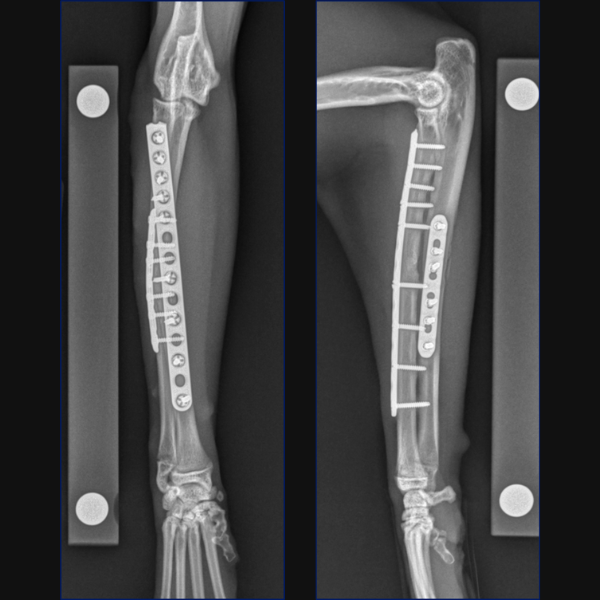

Radiographs at 3 weeks postoperatively showed maintained alignment and apposition, appropriate levels of activity and no evidence of implant-associated complications.